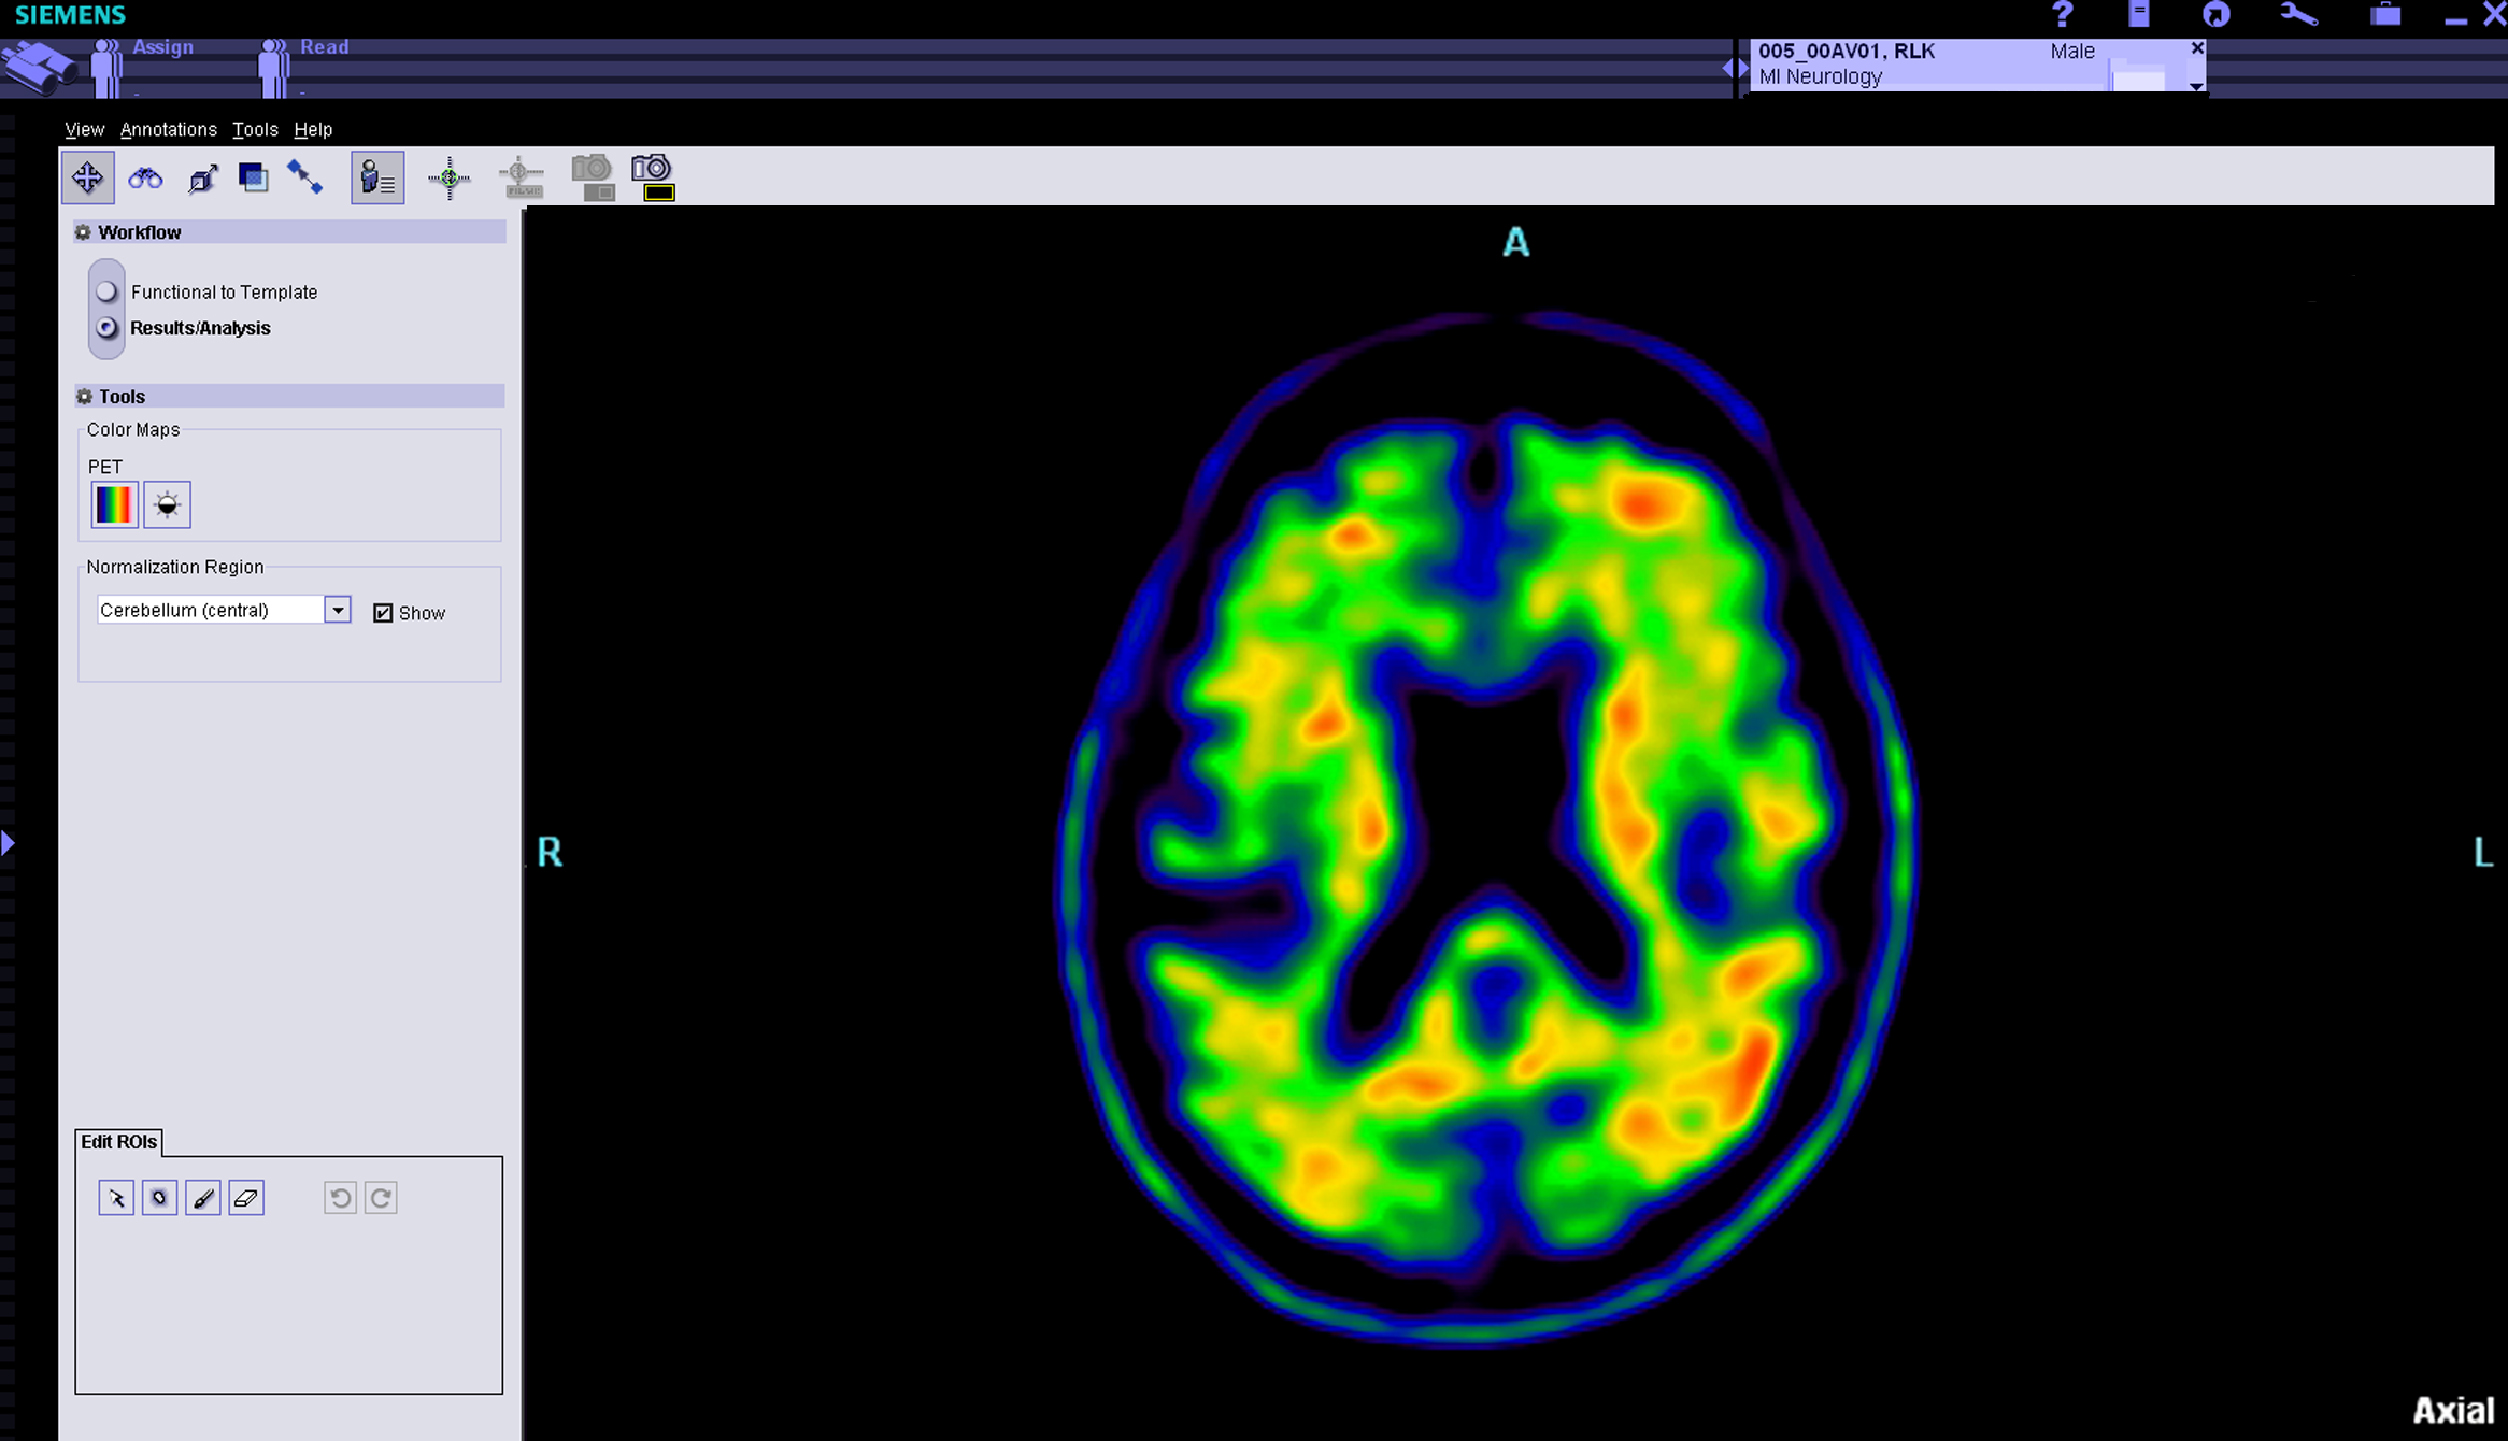

Eli Lilly and Company announced that the CMS has issued a draft decision proposing Coverage with Evidence Development for the use of beta-amyloid PET imaging agents. Beta-amyloid imaging agents are used to evaluate patients with cognitive impairment for Alzheimer's Disease and other causes of cognitive decline.[1]

An Amyvid (Florbetapir F 18 Injection) beta-amyloid scan is for use in adults with thinking or memory problems who are being assessed for Alzheimer's Disease or other causes of these symptoms. Amyvid is used by doctors in combination with other tests. A positive Amyvid scan does not diagnose Alzheimer's Disease or other thinking or memory disorders. Amyvid is not approved to predict the development of dementia or other brain conditions in the future or for monitoring the effectiveness of treatments. Amyvid for intravenous use is supplied in 10 mL, 30 mL, or 50 mL multidose vials containing 500-1900 MBq/mL Florbetapir F 18.[2]